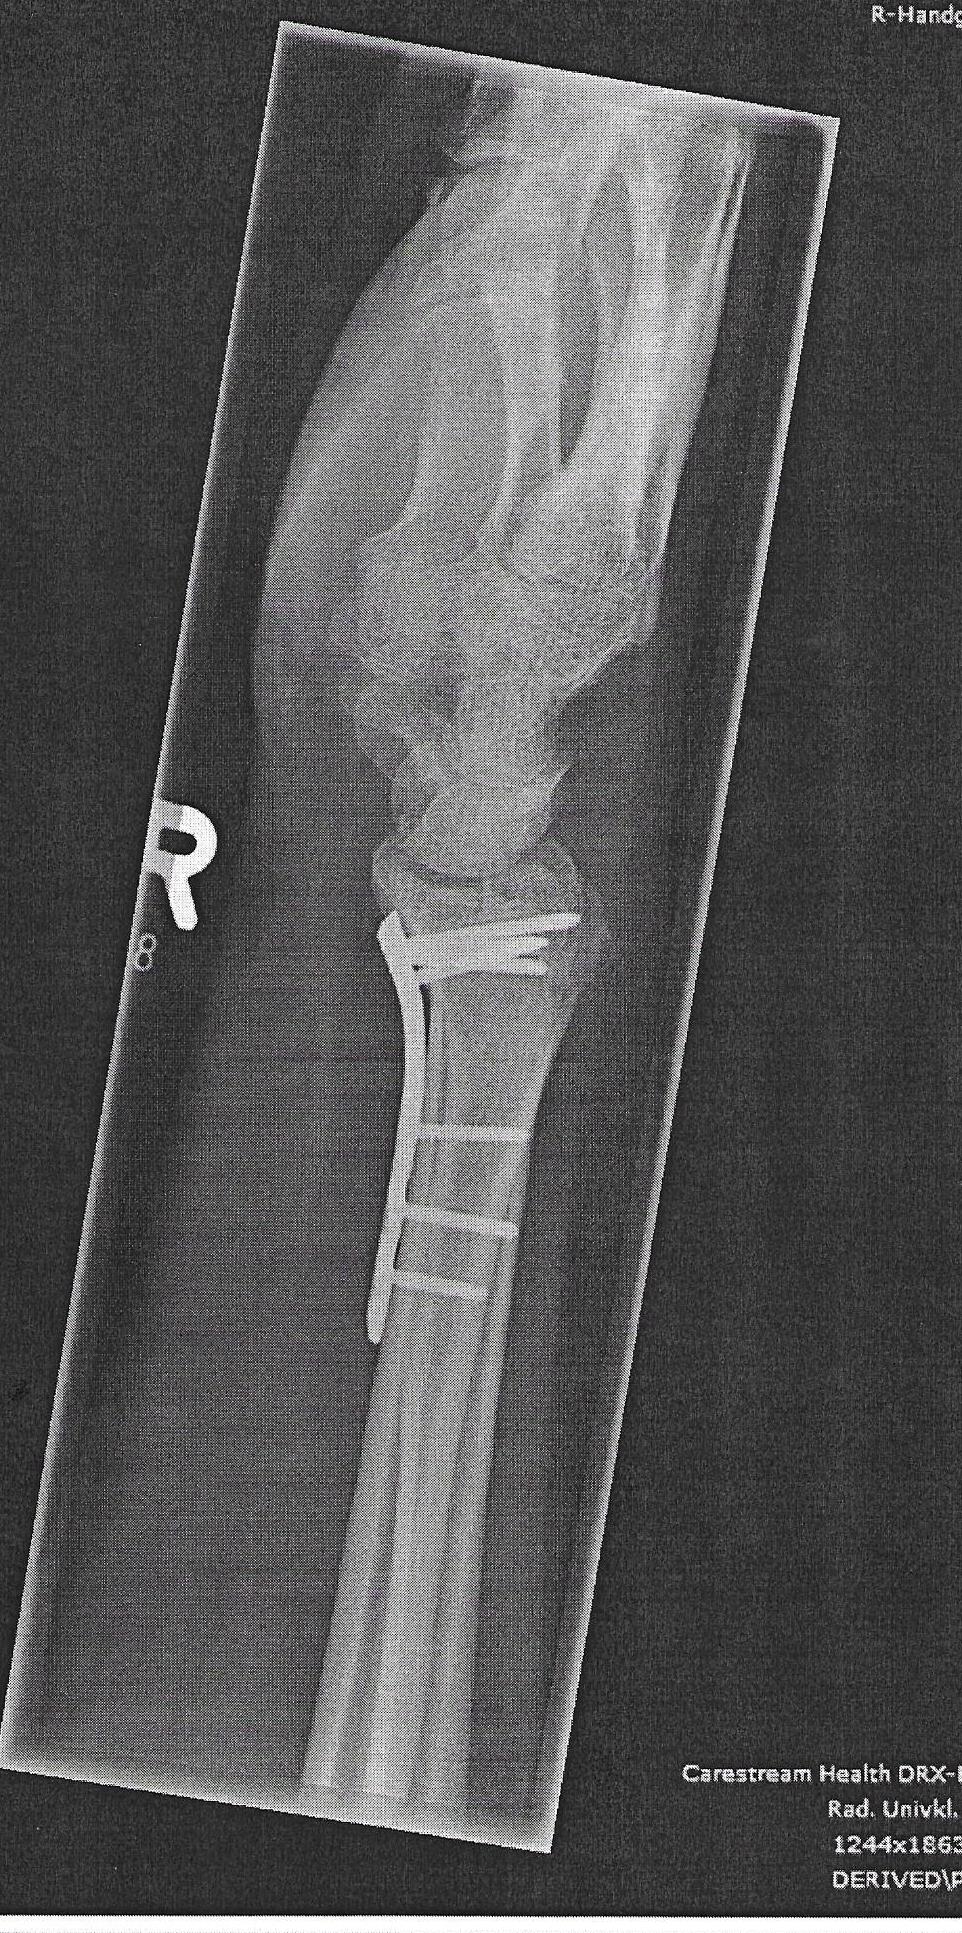

Nein, ist wirklich vergessen, dass vielleicht zu viel Gewebe zugewachsen ist, war auch 2 Jahre nach der Installation. Außerdem machen sie nicht "automatisch" ein Foto nach der OP.vergessene Schraube? die sieht man doch auf jedem billigen Rötgenbild..

Die kann ja nur absichtlich drin noch geduldet gewesen sein?

Dann haben Sie die anderen Bilder noch nicht gesehen diese sind auch hier in der Topikdas sieht ja echt überl ausSchnelle und Beste Genesung wünsche ich dir @Eddy der Belgier